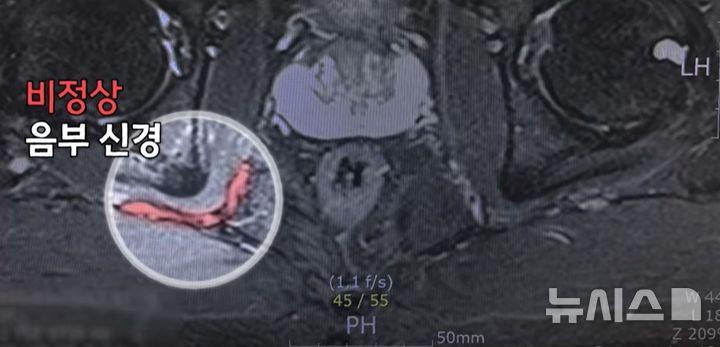

[서울=뉴시스] 비정상 음부신경. (사진= 한림대학교의료원 제공)